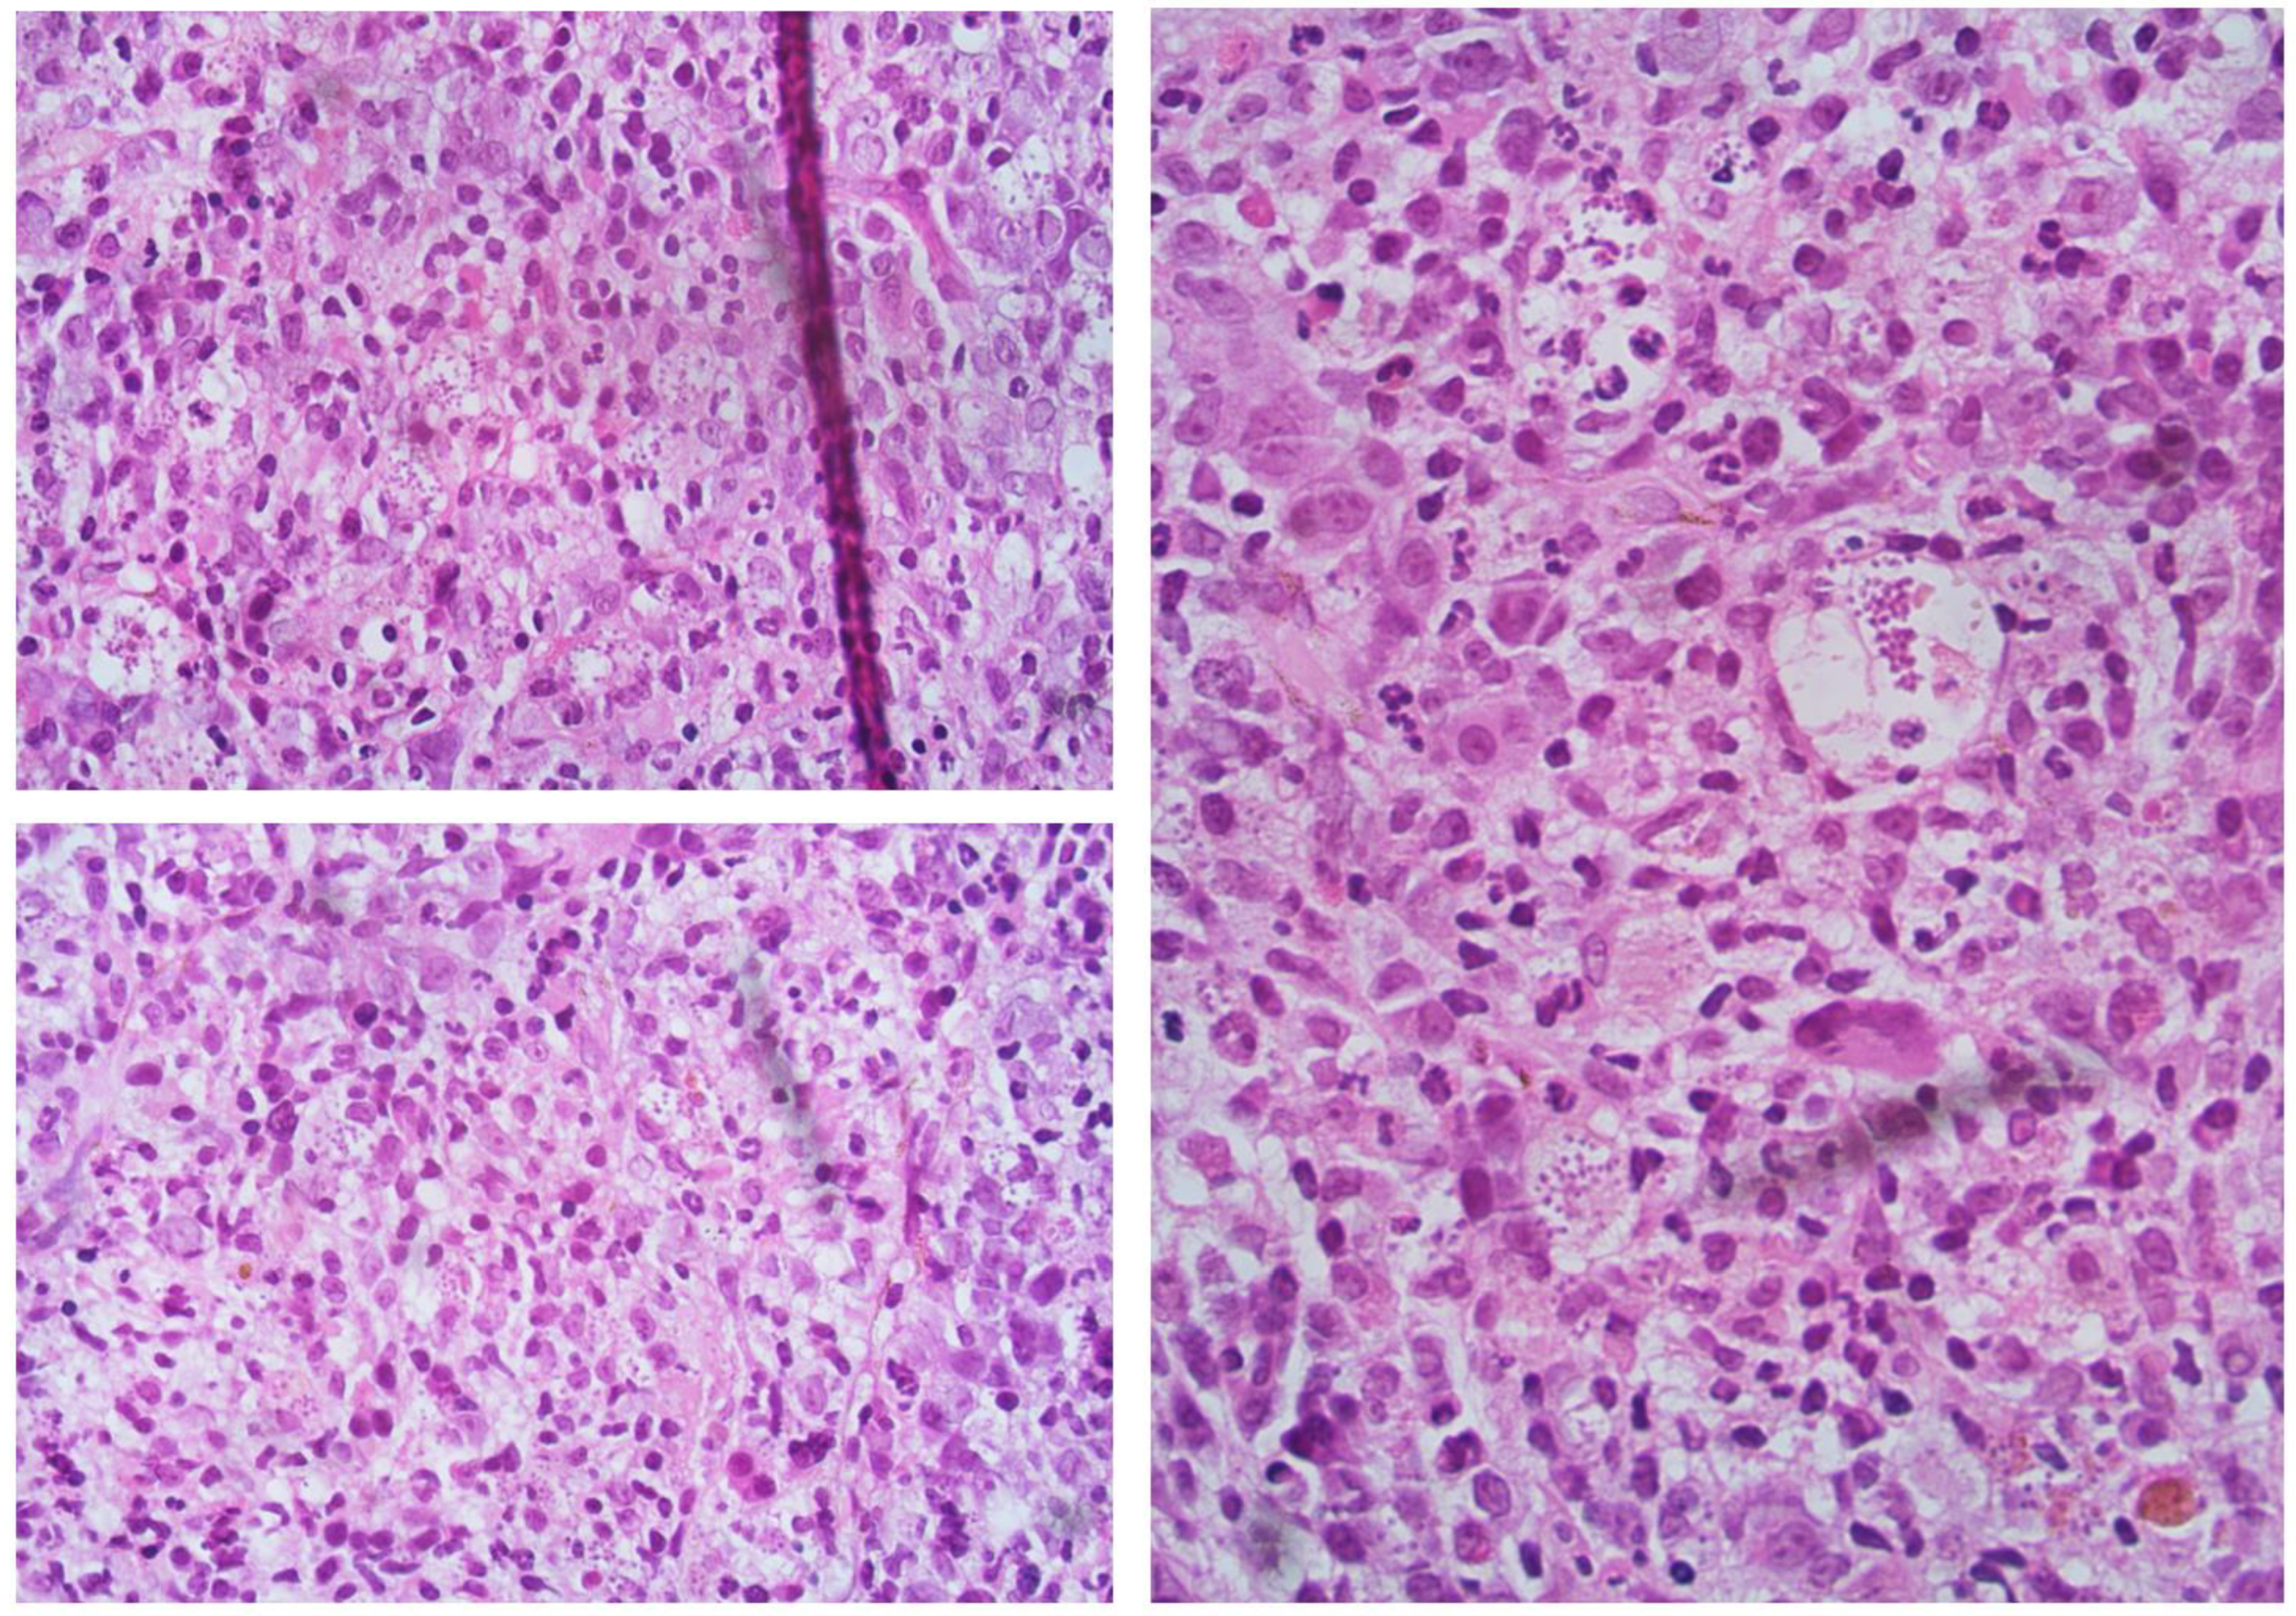

2. Case Presentation